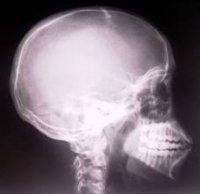

В Назарово (Красноярский край) с 1 декабря запретят использование единственного рентген-аппарата. Сейчас на три отделения Назаровской ЦРБ работает один стационарный рентген аппарат. Причем оборудование, выпущенное в 1987 году, давно устарело, не отвечает современным требованиям и с 1 декабря его запретят использовать.В этом году на базе отделений поселка Бор начнет работать травматологический центр, на его комплектацию по краевой целевой программе потрачено 4 миллиона рублей, однако приобретение рентген-аппарата по этой программе не планируется. Как рассказал главный врач Назаровской ЦРБ Борис Куликов, он надеется приобрести оборудование за счет экономии, полученной при реализации программы модернизации системы здравоохранения. Однако также велика вероятность того, что сэкономить не получится.